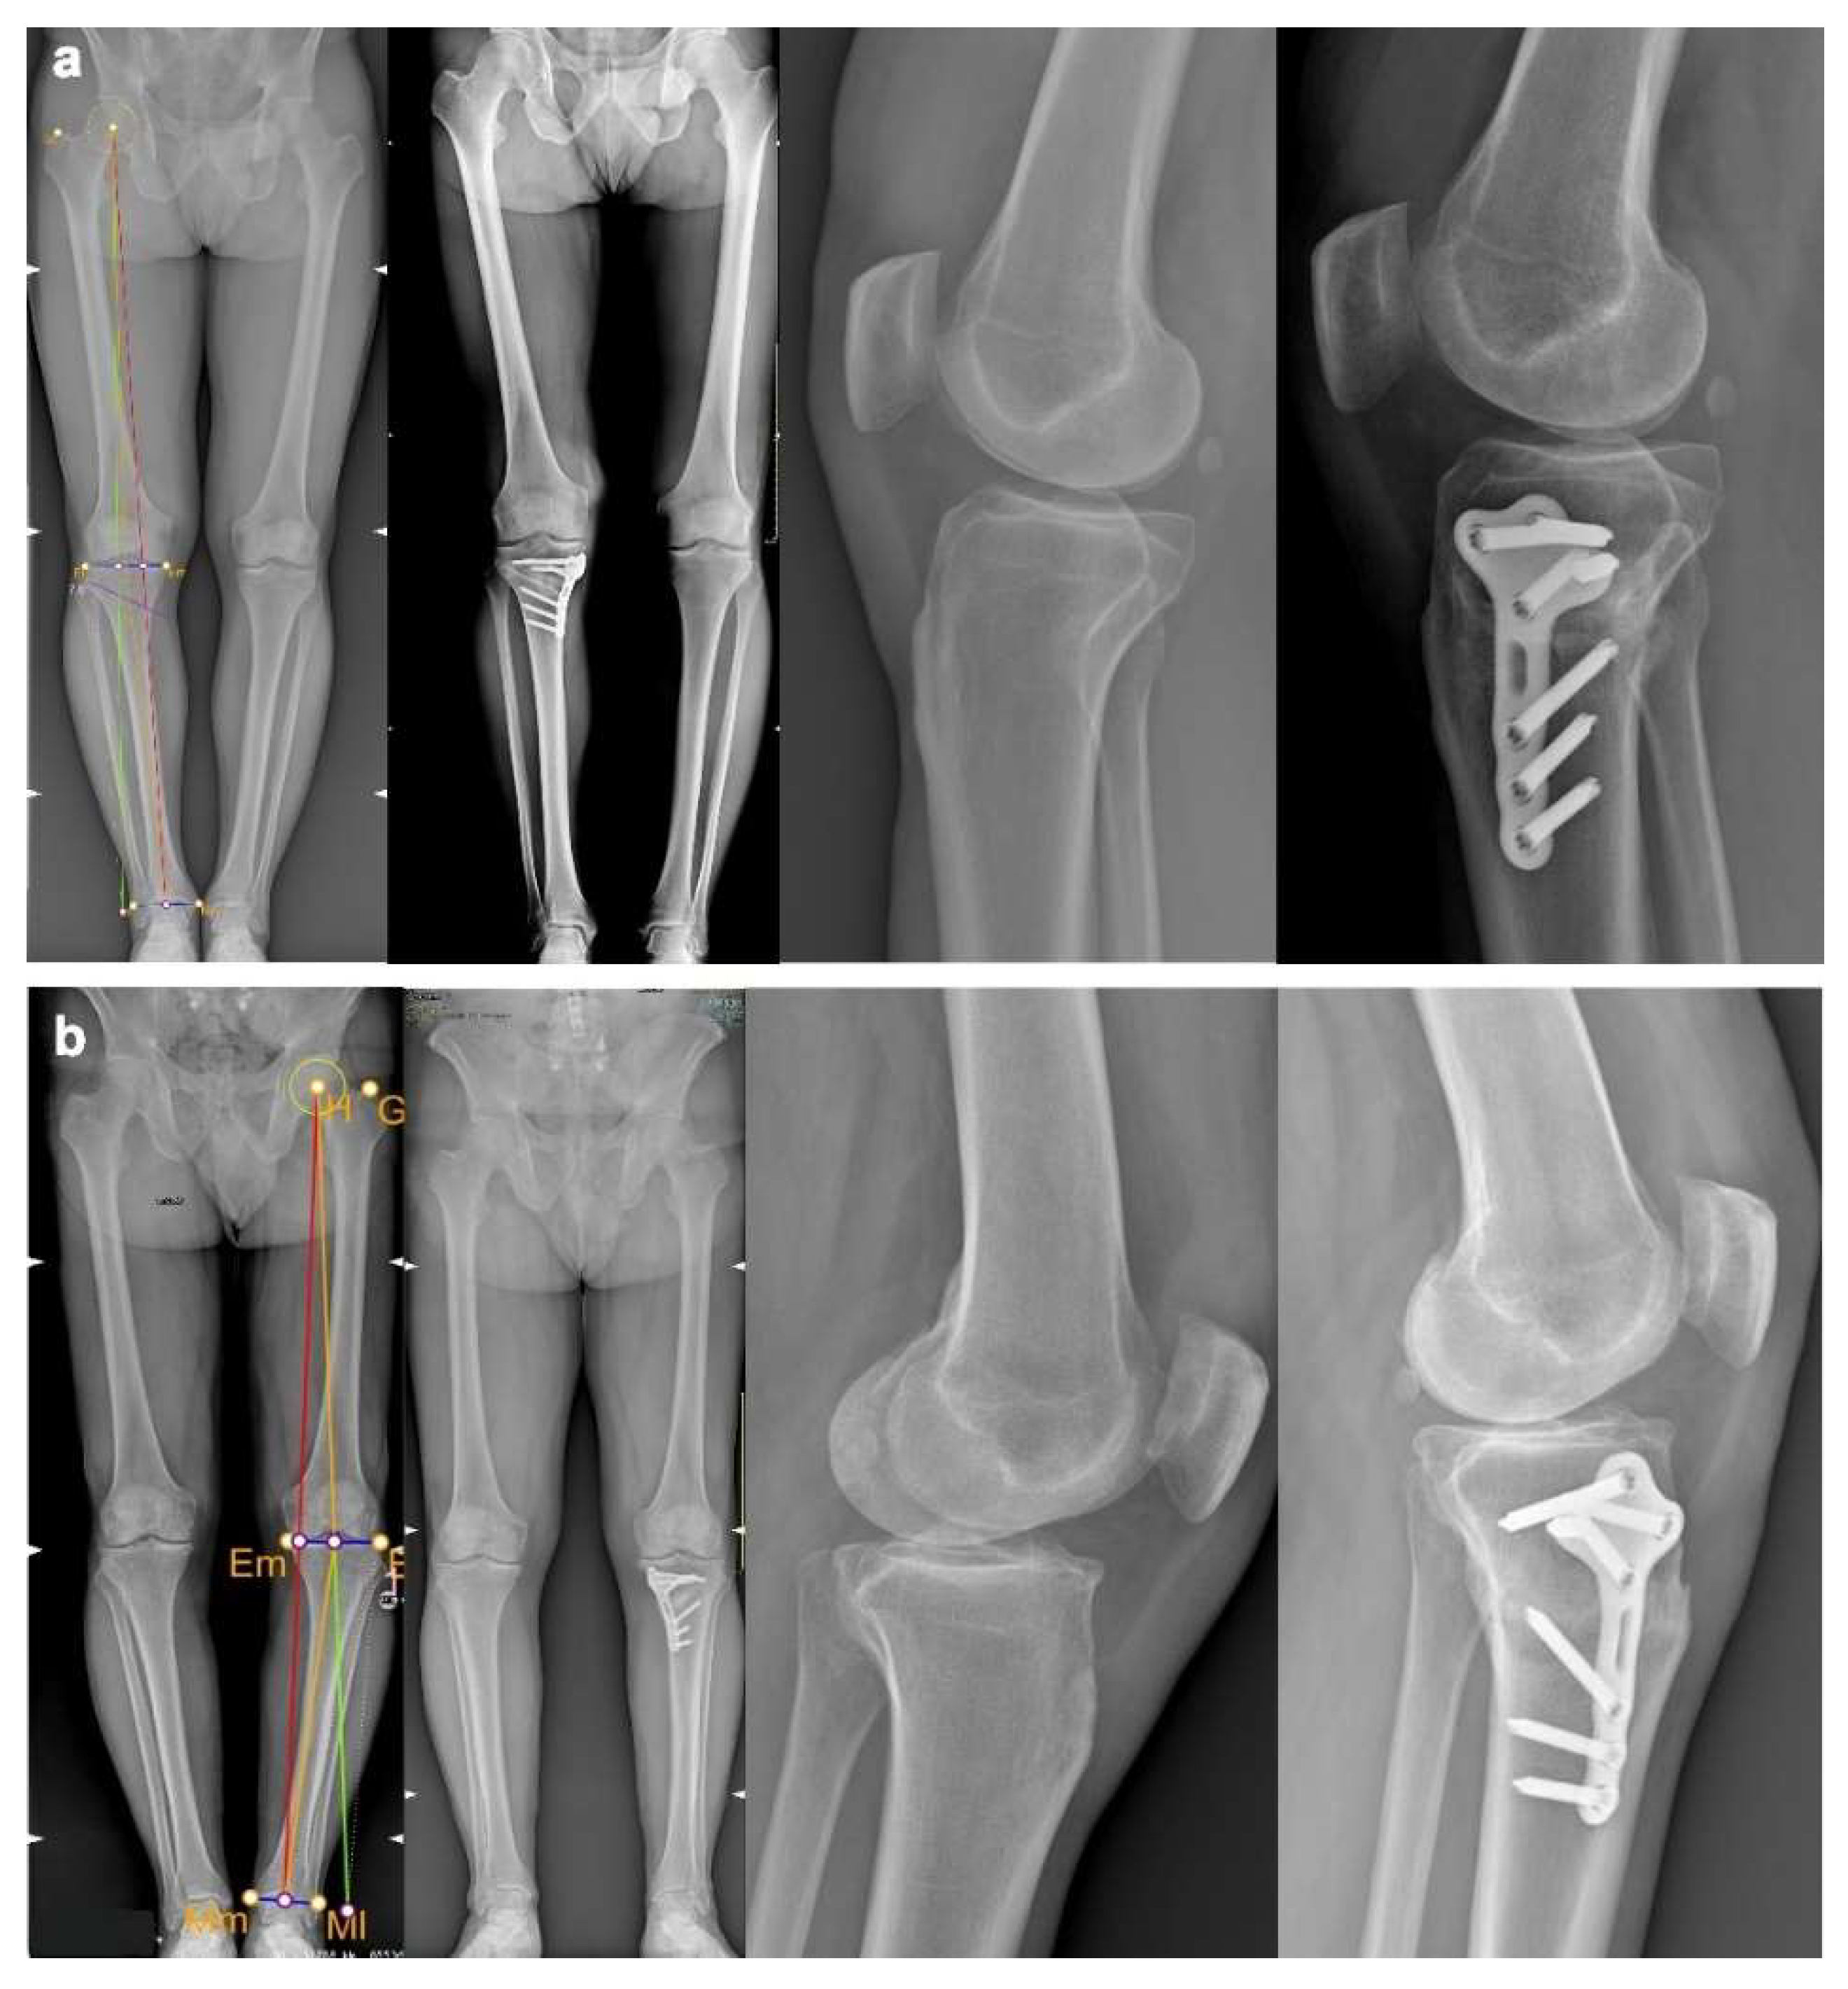

4.6. Preliminary Cases

| PATIENT ID | AGE | BMI | VAS PRE-OP | VAS POST-OP | KOOS TOTAL PRE-OP | KOOS TOTAL POST-OP | HKA PRE-OP | HKA PLANNED | HKA POST-OP | PTS PRE-OP | PTS PLANNED | PTS POST-OP |

|---|---|---|---|---|---|---|---|---|---|---|---|---|

| Patient 1 | 48 years old | 23.5 | 3 | 0 | 76 | 86 | 185.6° | 180.6° | 180.1° | 10° | 10° | 9.9° |

| Patient 2 | 60 years old | 27.7 | 3 | 0 | 51 | 74 | 190.1° | 180.3° | 181.9° | 8° | 8° | 8° |

| Patient 3 | 47 years old | 24.7 | 4 | 0 | 51 | 90 | 194.3° | 181.3 | 181.1° | 18° | 13.5° | 15° |